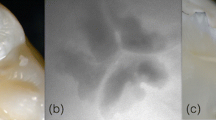

(A) Occlusal dental caries according to International Caries Detection and Assessment System (ICDAS) II criteria: (a–d) Score 1 (first visual change in the enamel) on the maxillary right second molar (#17). (e–h) Score 2 (distinct visual change in the enamel when viewed wet) on the maxillary right first premolar (#14). Score 3 (localized enamel breakdown) on the maxillary left second molar (#27). (a, e, i) Fluorescence image from the Qraypen C. (b, f, j) Fluorescence image from the Qraycam Pro. (c, g, k) Quantitative analysis of the Qraypen C image using QA2; (d, h, l) Quantitative analysis of the Qraycam Pro image using QA2. (B) Secondary dental caries according to the ICDAS II criteria: (a–d) Score 1 (first visual change in the enamel) on the maxillary left second molar (#27). (e–h) Score 2 (distinct visual change in the enamel when viewed wet) on maxillary left second molar (#27). (a, e) Fluorescence image from the Qraypen C. (b, f) Fluorescence image from the Qraycam Pro. (c, g) Quantitative analysis of the Qraypen C image using QA2. (d, h) Quantitative analysis of the Qraycam Pro image using QA2. (C) Proximal dental caries according to X-ray criteria: (a–d) Score 1 (radiolucency visible in the enamel) on the maxillary left first premolar (#24, arrow). (e–h) Score 2 (radiolucency restricted to the outer third of the dentin) on the maxillary left second premolar (#25, arrow). Score 3 (radiolucency extending to the middle third of the dentin) on the maxillary right first molar (#16, arrow). (a, e, i) Fluorescence image from the Qraypen C. (b, f, j) Bitewing radiograph. (c, g, k) Quantitative analysis of the Qraypen C image using QA2. (d, h, l) Quantitative analysis of the Qraycam Pro image using QA2.

Only the QLF parameter ΔFaver. showed significant agreement among the four QLF parameters analyzed in the present study, although the same sites were examined in both QC and QP images. This difference was attributed to the size (pixels) of the object photographed by the two devices. In general, the demineralization area of the occlusal surface is shown as a red or yellow area on QC images taken from a close distance, with finely divided pixels. In the QP image taken from a long distance, the pixels were displayed as black instead of a red or yellow area because the pixels could not be distinguished and, instead, were displayed together. Accordingly, our results demonstrated that QC images showing red/yellow regions had large ΔFmax values, while the QP images did not show the corresponding value and concomitantly showed low-intensity values.